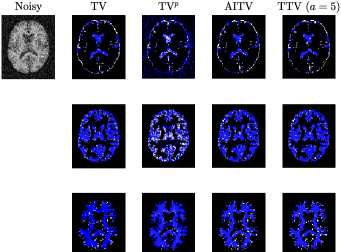

Refer to caption

Figure 3: Segmentation results of Figure 1(g) (after normalization) corrupted by Gaussian noise of mean 0 and variance 0.04. First row is CSF, second row is GM, and third row is WM.

Before applying the segmentation algorithms, the images in Figure 1 are normalized to [0,1]01[0,1] followed by Gaussian noise corruption. The retina vessel images are corrupted with Gaussian noise of mean 0 and variance 0.01. Table I reports the performances and times of the segmentation methods on the retina vessel images while Figure 2 shows some of their results. TTV (a=10,100)𝑎10100(a=10,100) has the highest DICE and Jaccard similarity indices across the three images although requiring about 80 seconds to complete, thereby being slower than TV and TVp. The brain images are corrupted with Gaussian noise of mean 0 and variance 0.04. Table II reports the performances and times of the multiphase segmentation, while Figure 3 shows the segmentation results of Figure 1(g). By its DICE and Jaccard similarity indices, TTV (a=1)𝑎1(a=1) is best at segmenting CSF across the four images while TTV (a=5,10)𝑎510(a=5,10) remains competitive against AITV in segmenting GM and WM. On average, TTV (a=1,5)𝑎15(a=1,5) is among the top two best-performing methods. Although it can be outperformed by AITV, it is at least three times faster. In Figure 3, we see that TTV (a=5)𝑎5(a=5) is most effective in segmenting CSF, especially compared to TV and TVp. Moreover, comparable to TV and AITV, it is able to identify most of the GM and WM regions. Overall, using TTV, the proposed method is able to effectively identify narrow, thin regions such as the retina vessels and CSF.